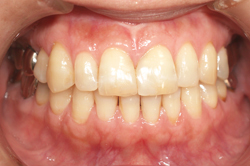

ラミネートベニア オールセラミックス110,000円(税込)

できるだけ歯を削らずにセラミックスの薄片を歯の表面に貼りつけます。生まれつき歯が変色していたり、歯が欠けたという悩みを解消します。より自然な色あいと形を再現し、永年の使用にも変色せず、健康的な白い歯の輝きで天然歯の美しさを保ちます。